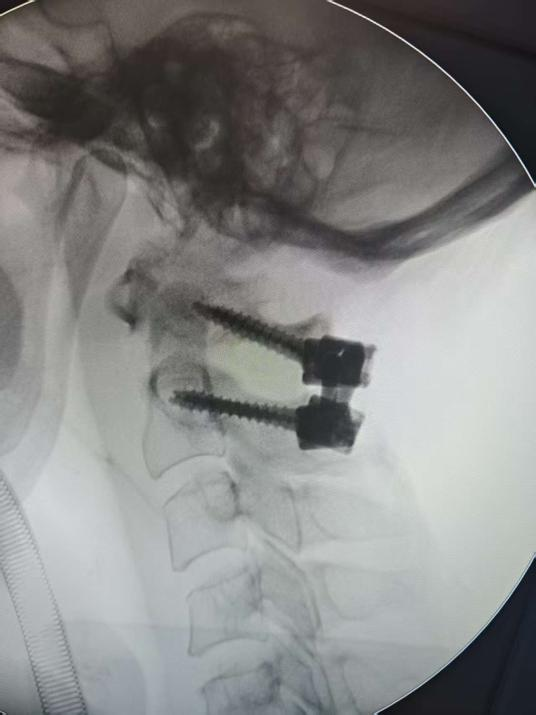

手术当天,团队在显微操作下精准置入螺钉,并采用交叉棒固定融合术,恢复了寰枢椎的解剖关系,为上颈椎提供了稳固支撑,还最大限度地保留了颈椎的活动度。

整台高难度手术仅用时1小时顺利完成,术后第2天,邝阿姨即能在床边坐起,疼痛明显减轻。